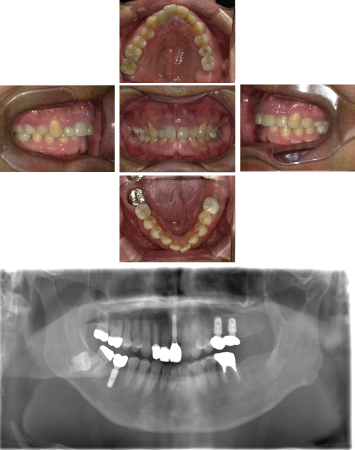

70代 女性 インプラント治療(GBR)

| 年代・性別 | 70代・女性 |

|---|---|

| 主訴 | 抜歯適応になってしまった所にインプラント治療希望。 |

| 部位 | 右上3・5(右上345のブリッジ)、右下6・7 左上4・6(左上456のブリッジ)、左下6・7 |

| 治療期間 | 約14ヶ月 |

| 費用 | ¥3,740,000(税込) |

| 副作用・リスク |

|